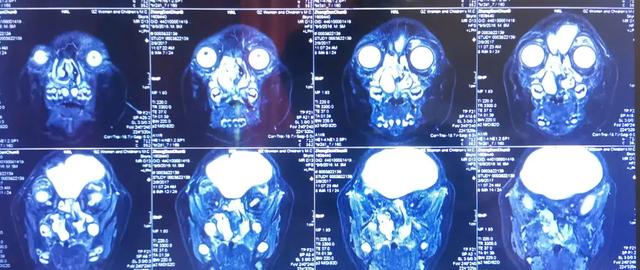

先天性后鼻孔闭锁,5000~8000 新生儿中的唯一,单侧比双侧发病的人多 1.6 倍。这么低概率的事情,却发生在我院耳鼻喉科一位 3 岁 10 个月的小患者身上——宝宝出生不久,就被发现患有先天性后鼻孔闭锁。

他的母亲回忆说,「宝宝出生时因为不能用鼻子呼吸,无法吸奶,和普通宝宝很不一样,立即带他去医院检查,被确诊为脑膜脑膨出、先天性后鼻孔闭锁、腭裂及皮罗氏综合征!」

经过入院检查后,张主任为患儿做了脑膜脑膨出切除加颅底修补手术。这是小宝宝经历的第二次手术,手术难度高,在张主任高超的技术下,宝宝术后恢复好,出院后也能正常呼吸及吸奶,这对父母总算放下心来。

张湘民主任联合本院口腔科刘全羲医生给患者进行了第四次手术治疗,术中应用到国际先进的内镜系统及离子技术,包括 storz 手术显示系统、storz 内镜及德国 sutter 射频系统等。